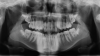

The maxillary right permanent centralincisor had a delayed eruption of 1½ years compared to its homologous incisor, and it was anteriorly displaced due to insufficient space in the premaxilla. Removal of the maxillary deciduous canines was indicated to unravel the crowding. An apically positioned flap of the impacted right central incisor was made to facilitate its eruption (Figure 5 and Figure 6). The case was worked up to plan an active phase l treatment, consisting of palatal expansion and the use of sectional fixed appliances in the upper arch. A transverse deficiency without posterior crossbite was identified, and therefore palatal expansion with a bonded expander was planned to widen the premaxilla (Figure 7 and Figure 8). A two-by-four fixed appliance system (brackets in the four maxillary anterior teeth and bands on the maxillary first molars) was used to align the maxillary teeth. The gingival margin of the retained maxillary right central incisor was slightly more apical than the left one, which erupted as expected (Figure 9 and Figure 10). Figure 11 shows a panoramic radiograph taken after completion of phase 1 treatment.

Fig 5. After performing an apical positioned flap, exposure of the impacted right central incisor was performed, frontal view (Fig 5) and occlusal view (Fig 6).

Figure 5

Fig 6. After performing an apical positioned flap, exposure of the impacted right central incisor was performed, frontal view (Fig 5) and occlusal view (Fig 6).

Figure 6